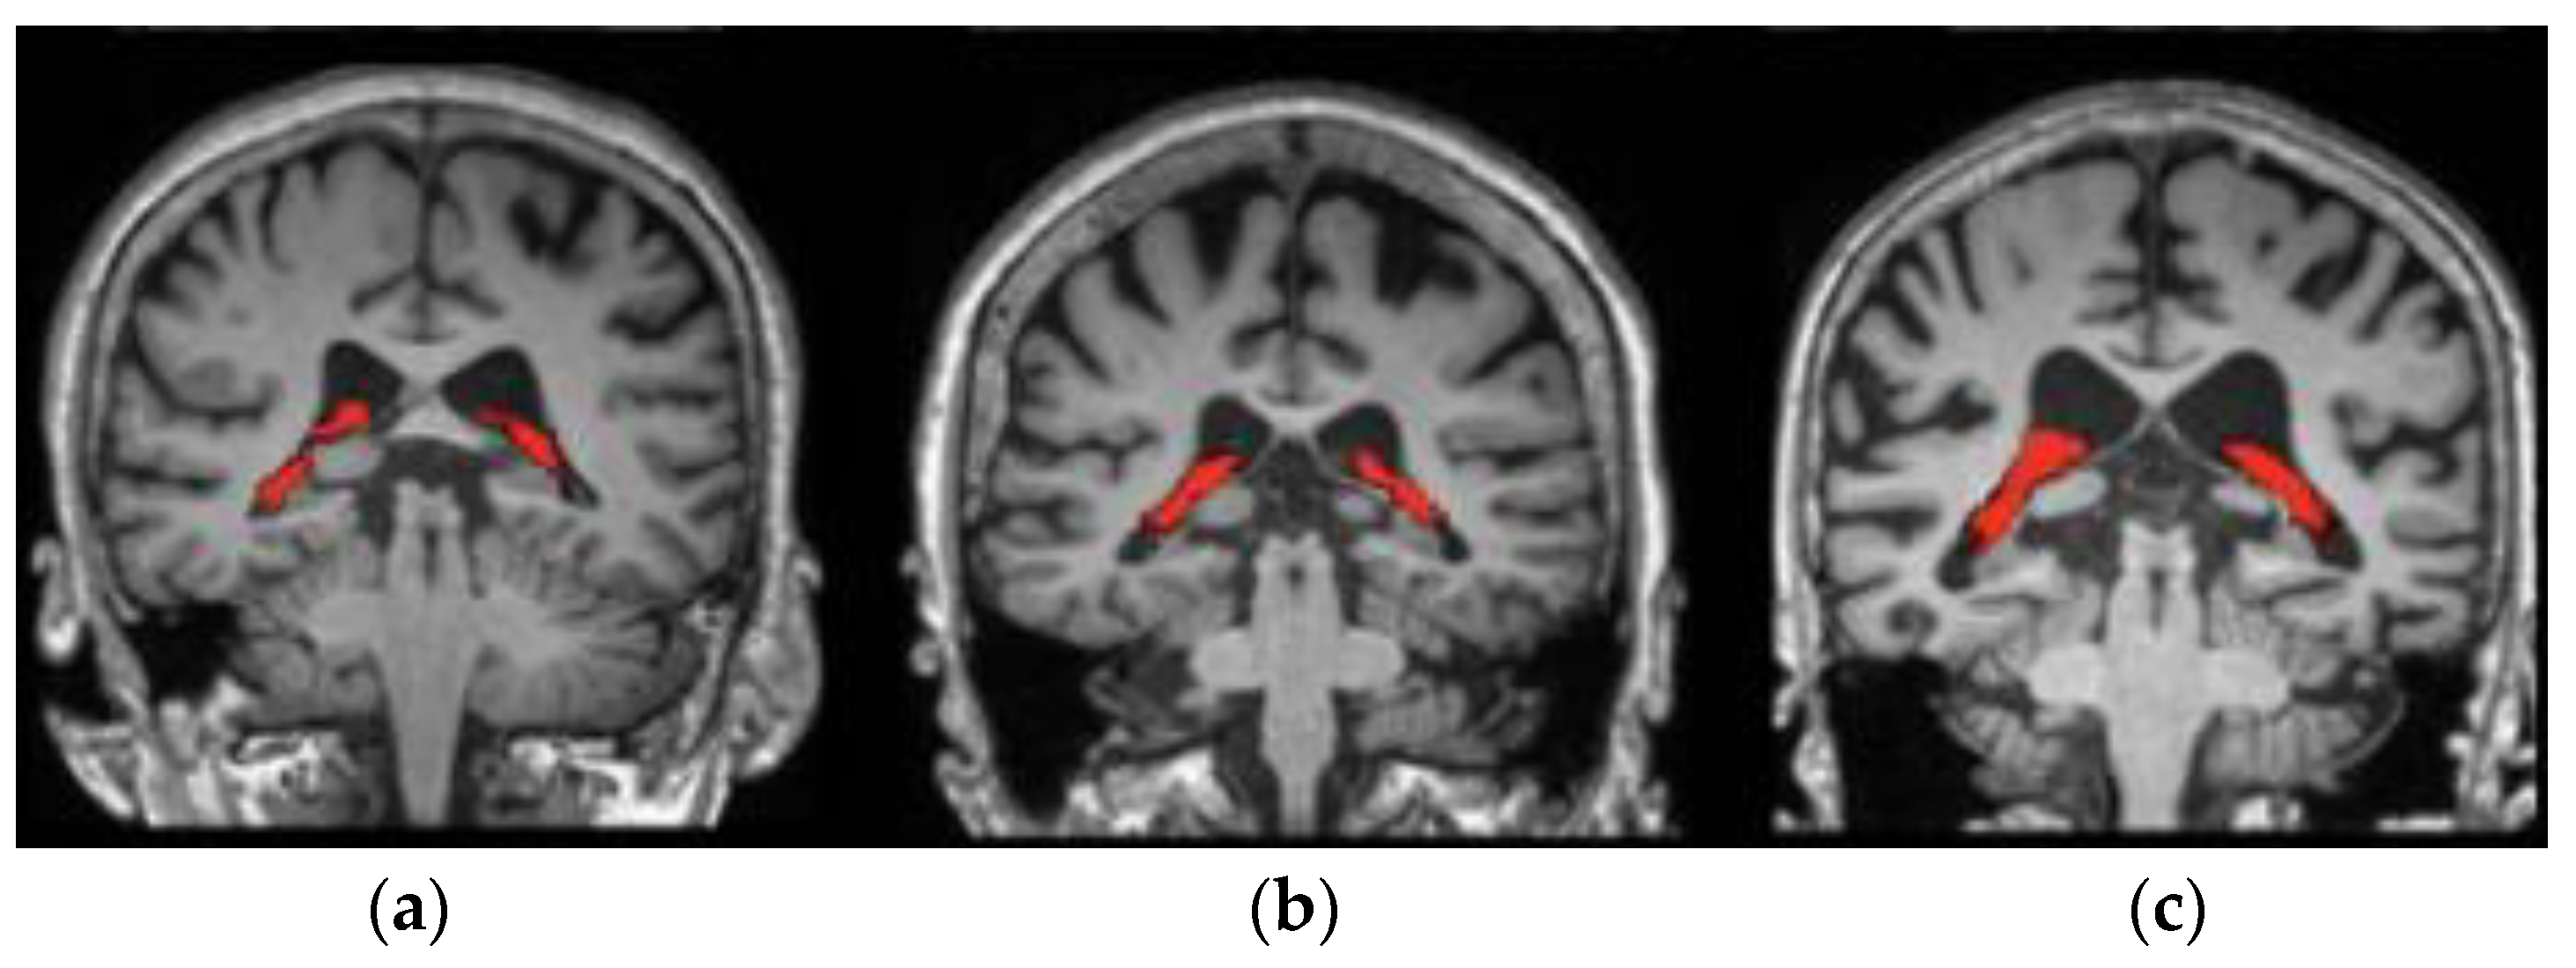

where S = c v 1 c v 2 255 , and   m = ( S p t 1 S p t 2 ) ^ 2 . The parameters S and m represent the colour similarity and distance between the seed points   S p t 1   a n d   S p t 2 , respectively. When the computed value of D i is maximum, the two pixels are very similar. As an outcome, a greater number of super pixels are segmented from the sMRI images, and the resultant image is presented in Figure 3. The hippocampus portions are marked in red colour in the respective sMRIs.

Figure 3. Segmented hippocampus portion from the sMRIs: (a) ADNI dataset, (b) real-time dataset, and (c) AIBL dataset.